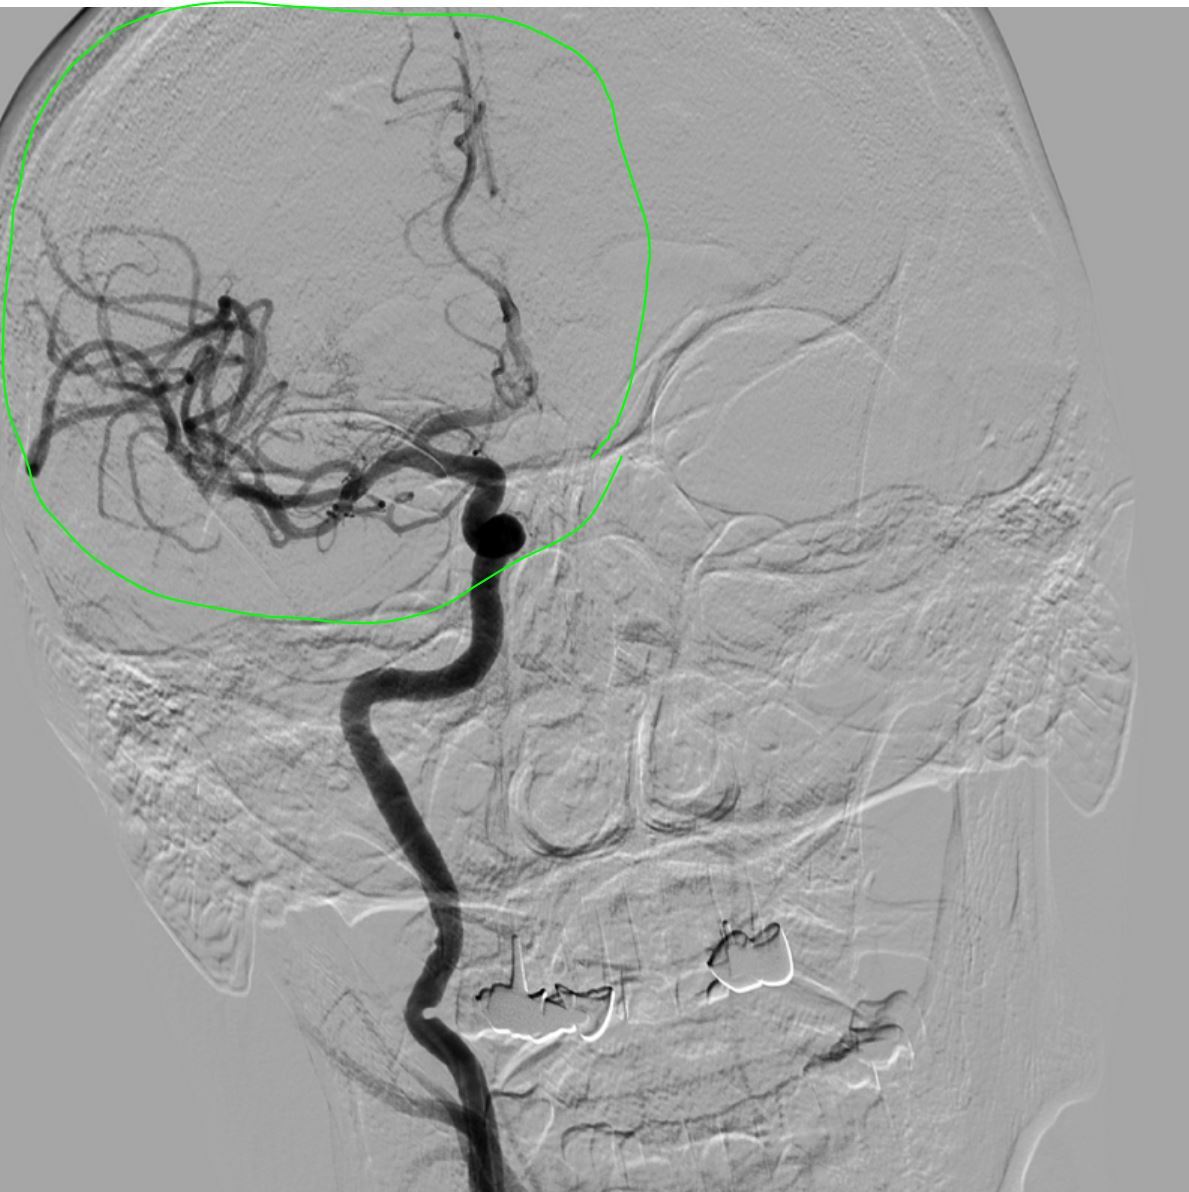

Уложили пациента, фиксировали. Далее все обычно, диагностика - церебральная ангиография - данные КТ подтвердились - устьевая окклюзия правой внутренней сонной артерии (ПВСА). Для справки - ВСА кровоснабжает примерно до 80% головного мозга (в рамках полушария), если проще - человек без нее "овощ" в большинстве случаев (если выживет).

Далее гайд катетер вместо диагностики, с учетом характера поражения решаю выполнить комбинированную методику = аспирационный катетер с одновременным использованием стента ретривера (усиленная методика ВСТЭ, я ее предпочитаю). Делаю т.н. "матрешку" = в гайд аспирационник, далее микрокатетер и проводник для реканализации и заведения "микрика". Все получилось без особых усилий. После заведения микрокатетера провел стент ретривер (для извлечения тромба), раскрыл его, удалив микрик, заякорился и максимально, как мог подвел на аспирации аспирационный катетер (картинка ниже)

Далее делаю аспирацию с ретривером, дважды - минимальный прогресс, удалось только немного открыть ВСА:

Результат после двух попыток...

В итоге после 5 попыток кровоснабжение правого полушария полностью восстановлено. Общее время операции около полутора часов, удалено много красных плотных тромбов. Дырку в ноге зашил Ангиосилом.

Комбинированная техника ВСТЭ: Время 23:51;Тип техники SAVE;Аспирационный катетер React 68; Стент-ретривер Trevo 3,0*20; Целевой сосуд пВСА + пСМА;Кровоток AOL исх. 0; Кровоток AOL кон. 3; Количество попыток 5; Удалено большое количество плотных красных тромбов; Осл. Нет; Результат оптимальный;

Результат ВСТЭ: оптимальный; Восстановление перфузии (mTICI) 3; Тип процедуры ЦАГ +ТА +ТЭ; Гемостаз AngioSeal 8F;